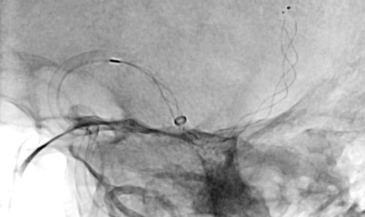

3. 脳血管内治療

脳梗塞の原因となる頸動脈狭窄症や、くも膜下出血の原因である脳動脈瘤に対しては、従来の脳神経外科的な手術(頸動脈内膜剥離術、脳動脈瘤クリッピング術)が行われてきましたが、より低侵襲で安全性や有効性が示されている脳血管内治療(頸動脈ステント留置術、脳動脈瘤コイル塞栓術)も可能になっています。

当院でも、脳血管内治療を積極的に行っておりますが、治療方針については、脳神経外科と連携し、患者さんとご家族にとって最適な治療が選択できるよう努めています。

その他、頭蓋内外の動脈の血管形成術や頭頸部の腫瘍に対する塞栓術など、幅広い脳血管内治療を行っています。